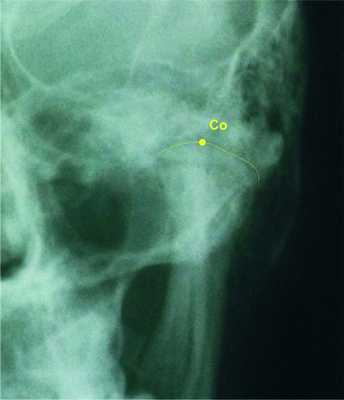

2. Определение цефалометрических точек, необходимых для наших анализов (рис. 1). Рисунок 1. Цефалометрические точки, использующиеся для разработки графических моделей. 2.1. Точка Lo (lateroorbitalae — dextra et sinistra) — пересечение латерального орбитального контура и больших крьльев клиновидной кости [6, 9, 11, 12]. 2.2. Точка Nc — на основе crista galli [6, 11, 12]. 2.3. Точка Co (condilion — dextra et sinistra) — самая высокая точка суставной головки НЧ [6, 9, 11]. 2.4. Точка Ме (mention) — нижняя точка подбородочного симфиза НЧ [6, 11, 12]. 2.5. Точкой О обозначаем середину сегмента Со-Со (см. рис. 1).

Для определения контура суставной головки необходимо знать анатомические околосуставные структуры. Контур суставной головки не очень отчетлив на ТРГ черепа в прямой проекции, и для большей точности мы рекомендуем данный участок дигитального рентгеновского снимка увеличивать с помощью компьютера [9] (рис. 4, см. на цв. вклейке). Рисунок 4. Увеличение контура суставной головки с помощью компьютерной обработки изображения.